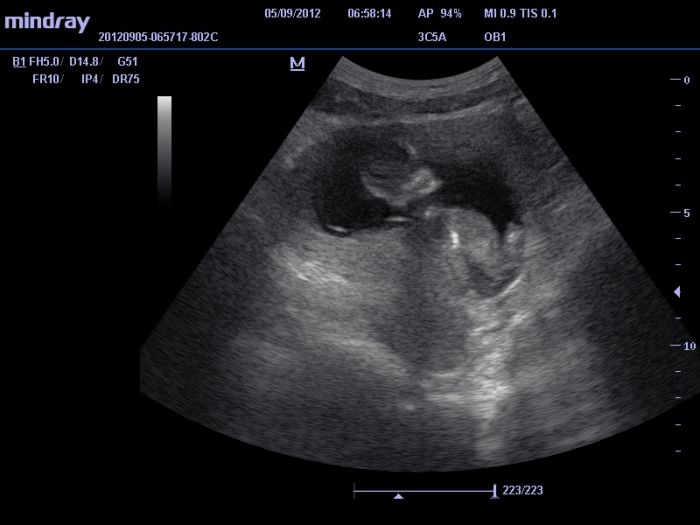

Dnes jsme byla na tom UZ a FECHO vyšetření a vše vypadá o.k., tak doufám a nechávám si opět rezervu pro případnou "jobovku". Pan doktor, který dělal vyšetření FECHO, byl naprosto úžasný, nadšený z každého dobrého výsledku, který našel, byl tak nadšený, jako by byl malý jeho